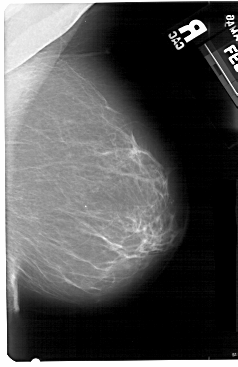

A_1493_1.RIGHT_CC

RIGHT_CC LINES 5491 PIXELS_PER_LINE 3301 BITS_PER_PIXEL 12 RESOLUTION 43.5 NON_OVERLAY